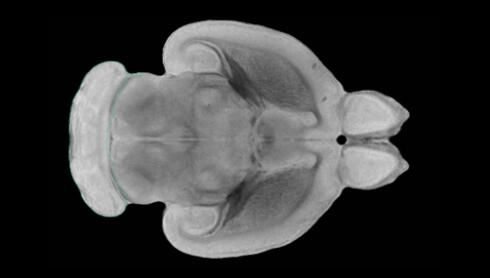

隨著機(jī)體年齡增加,肌肉和關(guān)節(jié)都會(huì)變得僵硬,這就會(huì)使得日?;顒?dòng)變得更加困難,本文研究表明,我們的大腦也是如此,與年齡相關(guān)的大腦僵硬對(duì)大腦干細(xì)胞的功能或許有著重要影響。文章中,研究人員對(duì)年輕和老化大鼠的大腦進(jìn)行研究闡明了年齡相關(guān)大腦僵硬對(duì)少突膠質(zhì)前體細(xì)胞(OPCs,oligodendrocyte progenitor cells)功能的影響。OPCs是一類對(duì)維持正常大腦功能非常重要的大腦干細(xì)胞,其對(duì)于髓磷脂的再生也非常重要,髓磷脂是神經(jīng)組織周圍的脂肪鞘,在多發(fā)性硬化癥中髓磷脂的再生常常會(huì)被損傷,機(jī)體老化對(duì)這些細(xì)胞的影響常常會(huì)誘發(fā)多發(fā)性硬化癥的發(fā)生,這些細(xì)胞的功能在老化的健康人群中同樣會(huì)下降。

為了確定老化OPCs的功能缺失是否可以被逆轉(zhuǎn),研究人員將來(lái)自老化大鼠機(jī)體的老化OPCs轉(zhuǎn)移到了年輕大鼠柔軟的海綿狀大腦組織中去,值得注意的是,這些老化的大腦細(xì)胞能夠重新恢復(fù)活力,其行為非常像年輕更加強(qiáng)壯的細(xì)胞。這項(xiàng)研究中,研究人員在實(shí)驗(yàn)室中開(kāi)發(fā)出了具有可變僵硬程度的新型材料,并在受控環(huán)境下研究這些材料的生長(zhǎng)及其對(duì)大鼠大腦干細(xì)胞的影響,這些材料能被工程化改造具有和年齡或老化大腦相似的柔軟程度。